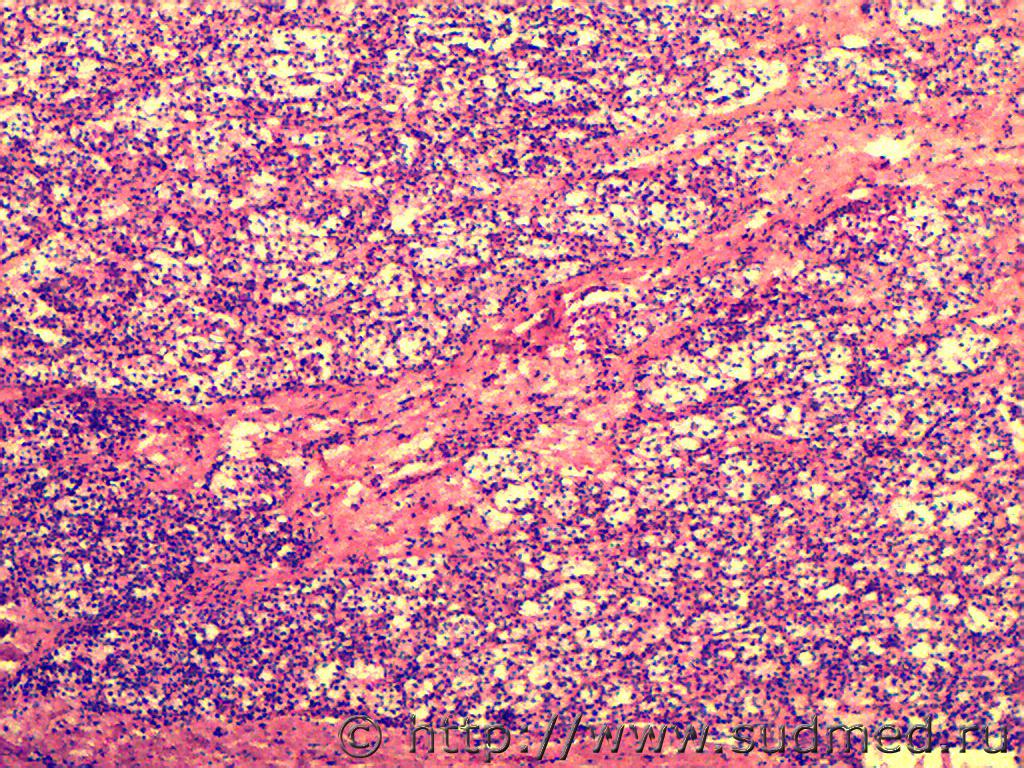

Язва-рак желудка.